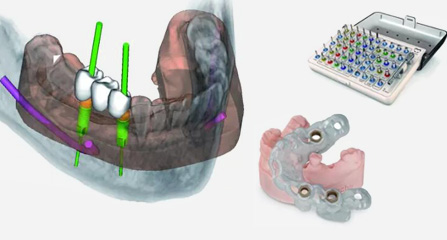

麦芽口腔着眼于全链条的数字化诊疗解决方案,与德国Kavo、瑞典Nobel、韩国奥齿泰、中国康泰健等国际知名齿科品牌合作,建立“深圳数字化口腔联盟”,应用全数字化口腔模式,从CBCT数据提取、AI口扫取模、AI智能口腔体检、数字化分析模拟与方案设计、3D打印、CAD/CAM椅旁加工以及手术模拟导航等,全流程打通数字化口腔精确诊疗的各个环节,实现麦芽数字化口腔诊疗体系新升级。

云端3D打印 导板精确辅助

动态导航监测 精确控制植入路径